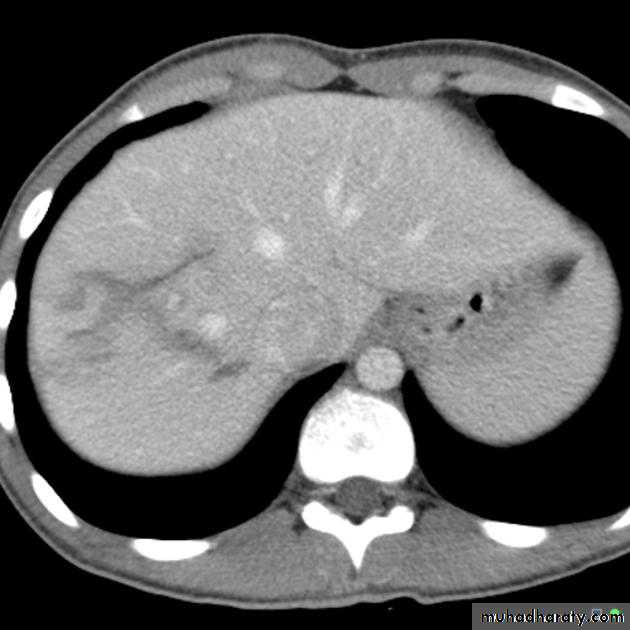

Multiple masses

CT scan